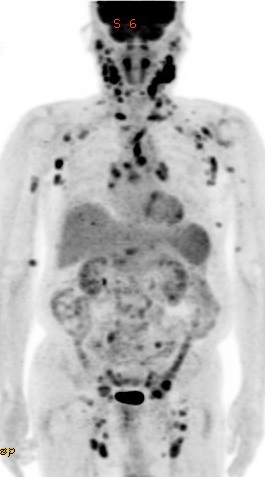

À§±Ë¾ç¿¡ À§ ÁÖº¯ ¸²ÇÁÀýÀÌ °üÂûµÇ´Â °ÍÀº °¡´ÉÇÑ ÀÏÀÌÁö¸¸ ±Ë¾çÀÌ È£ÀüµÉ ¹«·Æ follow upÇÑ CT¿¡¼­ ¸²ÇÁÀýÀÌ °è¼Ó º¸¿´½À´Ï´Ù. ±×·¡¼­ PET¸¦ ½ÃÇàÇÏ¿´°í °æºÎ ¸²ÇÁÀýÀ» Æ÷ÇÔÇÑ ´Ù¹ß¼º glucose uptake°¡ º¸¿´½À´Ï´Ù. °æºÎ ÁøÂû¿¡¼­ mass°¡ ¸¸Á®Á³°í, needle biopsy¸¦ ÅëÇÏ¿© follicular lymphoma, 3a·Î È®ÀÎÇÏ¿´½À´Ï´Ù.

¿ä¾àÇϸé systemicÇÑ follicular lymphoma¿Í ¾ç¼º À§±Ë¾çÀÌ ÀÖ¾ú´ø ȯÀÚÀÔ´Ï´Ù. µ¹ÀÌÄÑ »ý°¢Çϸé CT¿¡¼­ º¹ºÎ ¸²ÇÁÀýÀÌ º¸Àδٰí ÇÏ¿´À» ¶§ À§¾Ï ¸²ÇÁÀý ÀüÀ̸¸ °í·ÁÇÒ °ÍÀÌ ¾Æ´Ï°í Àü½Å ¸²ÇÁÀý ÁøÂûÀ» Çß´õ¶óµµ ¸î ÁÖ »¡¸® follicular lymphoma¸¦ Áø´ÜÇßÀ»Áö ¸ð¸£°Ú½À´Ï´Ù.